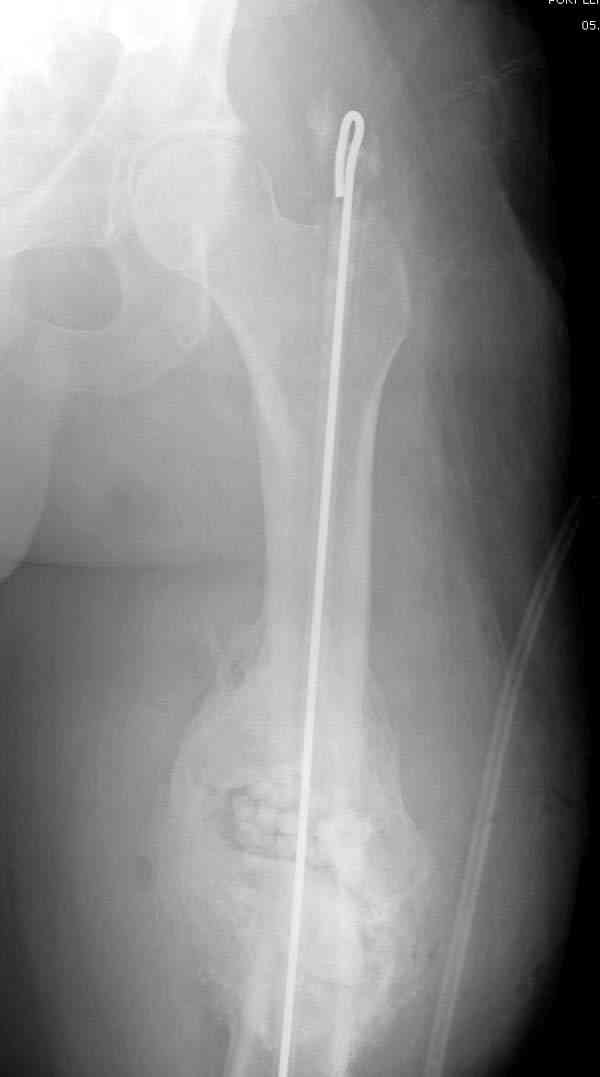

На ренгенограмме явный остеомиелит с секвестром, секвестерэктомия из медиального доступа и замена старого антибиотического гвоздя на новый.

После трех дней ваккуумного дренажа, из латерального доступа удаление остатков старых антибиотичеких бус, закрытие медиальной раны с наложением ваккуумирования латерально. В следующий раз, через пару дней надеемся закрыть рану.

удаление

подготовка гвоздя